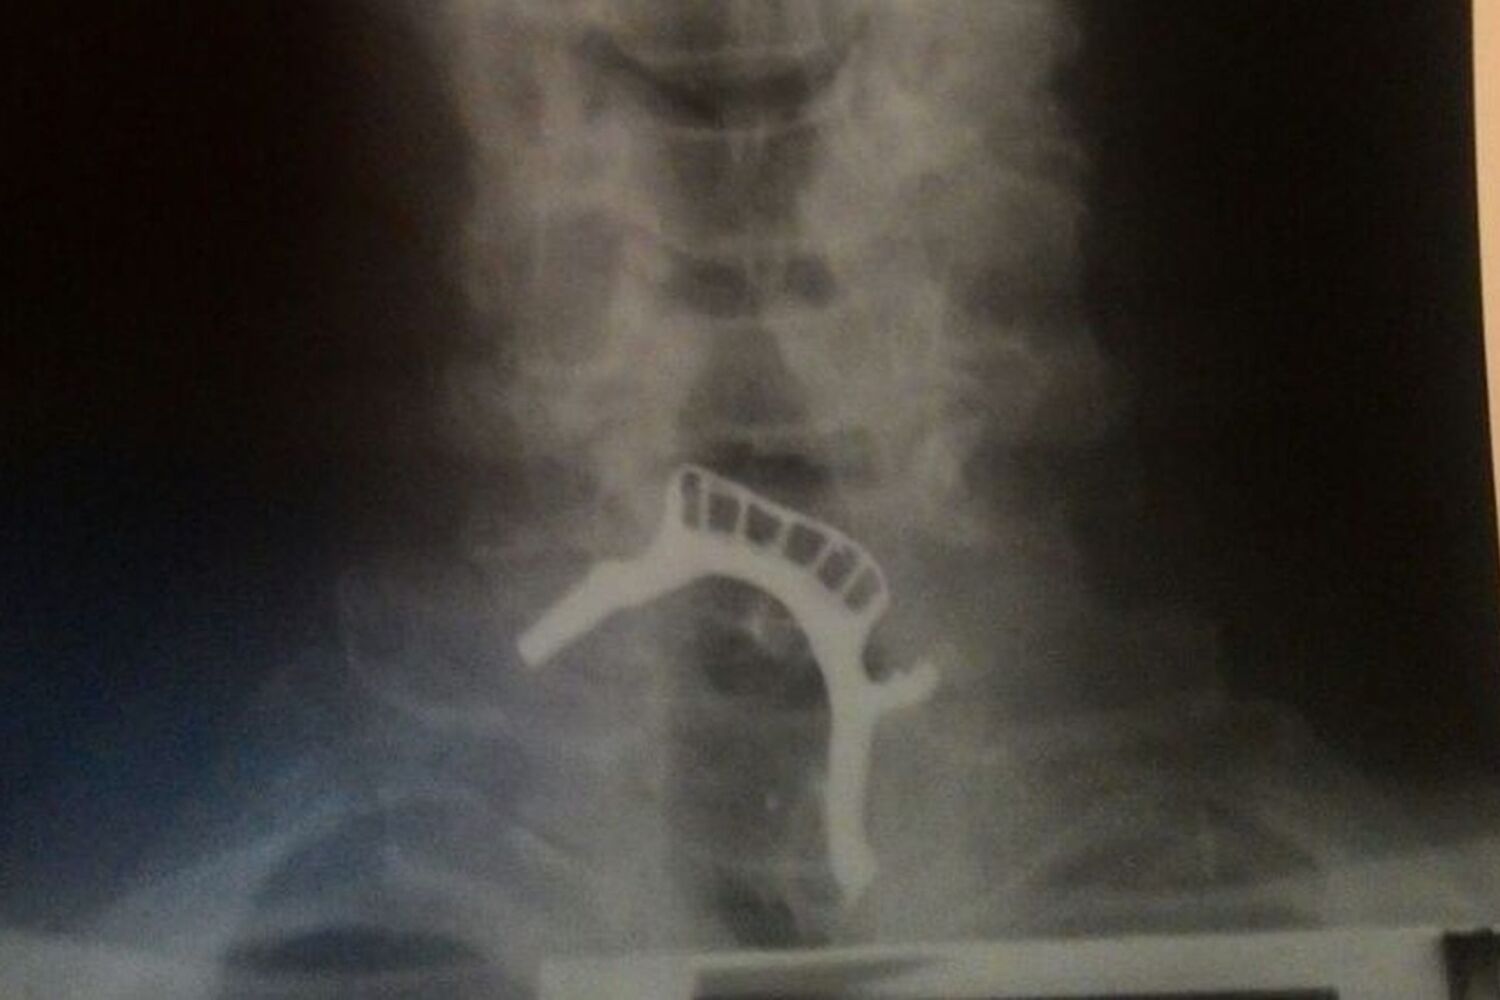

Segundo o site G1, que falou com a filha de Antonio, foi feito um raio-X para verificar que a dentadura estava presa. Foi dito à família que era preciso um aparelho de endoscopia para verificar a situação e de que forma seria possível retirar a prótese. No entanto o hospital não dispunha do aparelho há vários dias.